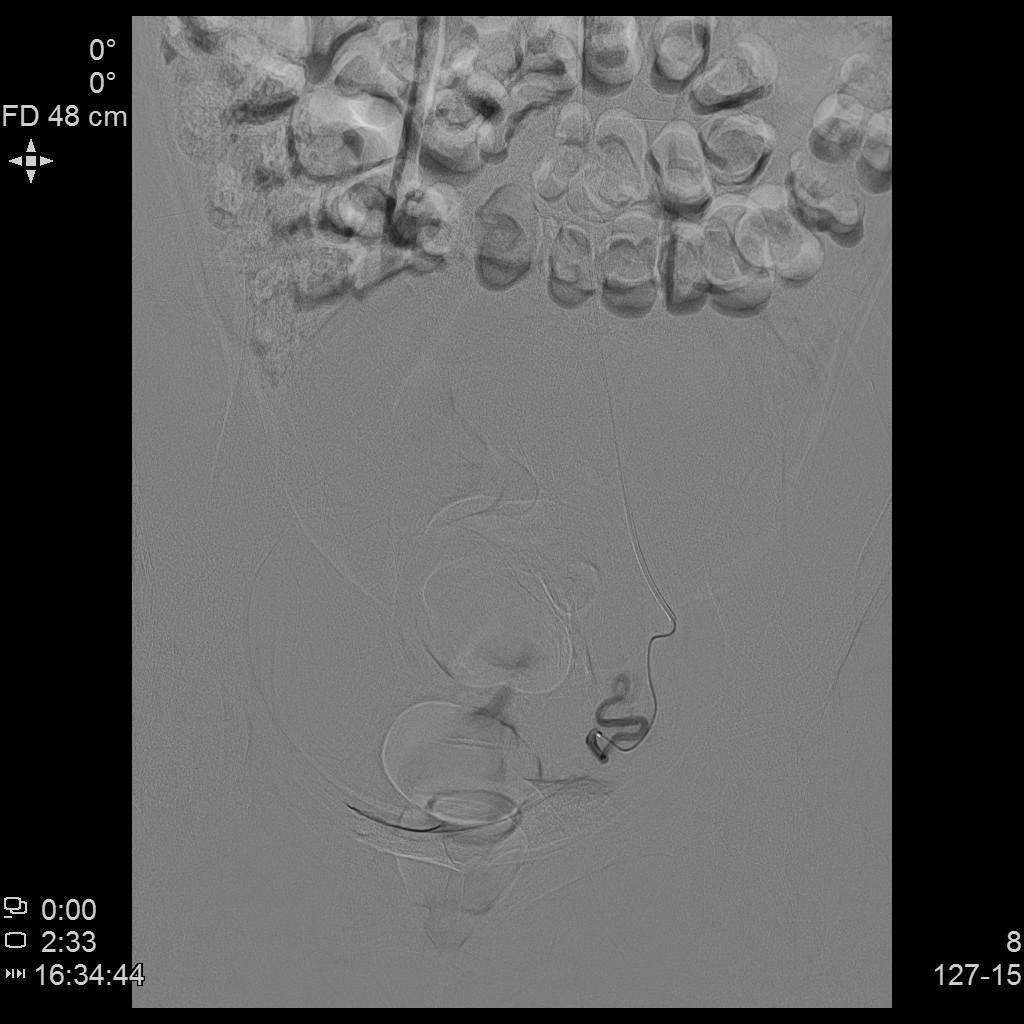

- 经桡动脉入路,分别超选择插管至双侧子宫动脉造影+子宫肌瘤栓塞治疗。

左侧子宫动脉造影